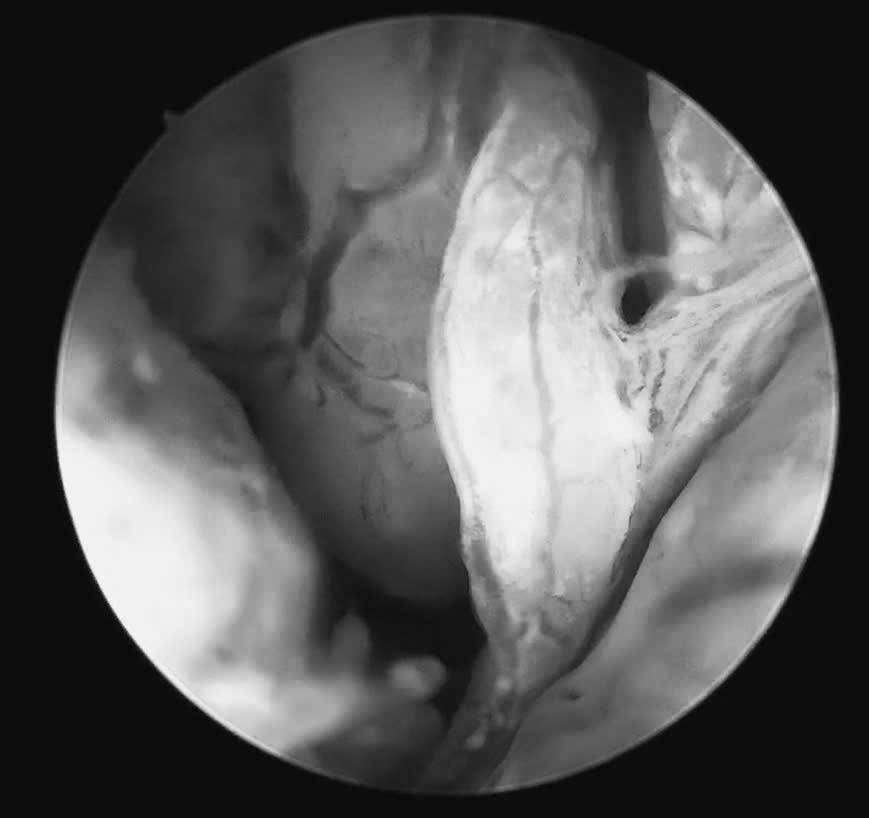

ngan-vang.png

Nội soi phát hiện sớm bệnh nâng cao chất lượng sống - Ảnh BVCC

Trước tình huống đó, tại Khoa Khám Phụ khoa Tự nguyện, bệnh nhân được tư vấn thực hiện soi buồng tử cung sinh thiết bằng ống soi nhỏ, một phương pháp cho phép đánh giá trực tiếp buồng tử cung mà không làm tổn thương màng trinh. Ca thủ thuật được ThS.BSCKII Nguyễn Biên Thùy – Trưởng khoa Khám Phụ khoa Tự nguyện trực tiếp thực hiện.

Quá trình soi diễn ra an toàn, nhẹ nhàng. Bệnh nhân hoàn toàn tỉnh táo và có thể quan sát trực tiếp hình ảnh buồng tử cung trên màn hình: niêm mạc nham nhở, tăng sinh không đồng đều, nhiều mạch máu bất thường, những dấu hiệu gợi ý tổn thương ác tính. Mẫu sinh thiết được lấy ngay trong quá trình soi để làm xét nghiệm mô bệnh học.